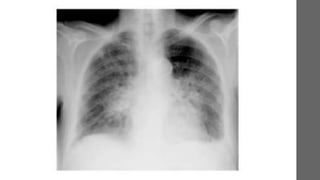

CASO CLÍNICO

•Identificação:

RLM, feminina, 54 anos, viúva, católica, dona de casa, natural e

procedente de Salvador.

• Queixa Principal:

Tosse há cerca de 3 meses

Anamnese

• HMA:

Paciente refere que apresenta tosse com expectoração mucóide

há cerca de 3 meses a tosse piorou, passando a apresentar expectoração amarelada

associada com dispnéia moderada. Após 1 mês, refere ter reiniciado o quadro de

tosse (desta vez seca) e dispnéia intensa, associado com febre vespertina diária (não

mensurada). Refere

perda ponderal de 15kg nos últimos 3 meses. Nega hemoptise, dor ventilatório-

dependente.

• Geral  REG, LOTE, emagrecida, mucosas hipocrômicas +/4+, anictérica,

acianótica.

• Cabeça e Pescoço  Linfonodos palpáveis em cadeias submandibular e

cervical anterior, medindo 1,5cm, consistência fibroelástica, móveis, indolores à

palpação. Orofaringe sem alterações.

• Sinais Vitais  PA: 130x90mmHg / FC= 117bpm / FR = 24ipm / Temp. 38,4 ºC

• AR  Tórax simétrico, sem abaulamentos, ou retrações costais. FTV sem

alterações. À Percussão som claro pulmonar. MV reduzidos globalmente com

roncos em base de Htx direito.

• ACV  Ictus visível e palpável no 6º EIC, BRNF, em 2 tempos, com

SS III/VI foco mitral irradiando para axila.

• Abd.  Plano, flácido, RHA +, indolor à palpação. Fígado a 5 cm do RCD, com

hepatimetria 8 cm. Baço não palpável; espaço de traube livre.